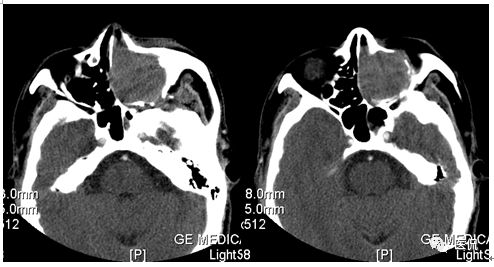

增强动脉期

CT平扫及增强示:左侧上颌窦及鼻腔可见软组织密度影,呈膨胀性生长,周围骨质压迫性吸收破坏,累及左眶,病灶密度不均匀,周边区可见点状钙化,增动脉期轻度强化,局部见小灶性稍高密度区,静脉期病灶内见不均匀明显强化,CT值最高达117HU,延迟期强化范围有所增大。

影像学表现呈软组织密度,多不均匀,表现为高低混杂密度,病变窦腔内息肉、血肿、坏死、感染共存,是病灶密度不均匀的主要原因,息肉反复出血、血管机化亦为其成因之一。病灶内钙化,可为团块状或小片状,可能为病变组织坏死后钙质沉着所致。由于病变组织内有大量炎性细胞浸润和丰富的毛细血管,增强后常有强化。有文献报道病灶增强中心区强化不明显,外周呈轻度强化,推测病灶内虽然血管丰富,但中心区容易出现血流动力学障碍,血管内常有血栓形成,中心区易发生出血坏死,另外,可能与增强扫描延迟时间选择不当有关。

本例病灶较大,周围骨质可见吸收破坏,并累及眼眶,病灶内少量钙化,增强扫描具有一定特征性,表现为动脉期轻度强化,局部见小灶性稍高密度区,静脉期病灶局部呈明显强化,CT值最高达117HU,延迟期强化范围有所增大,呈延迟渐进性强化的特点,推测为病灶内出血所致。